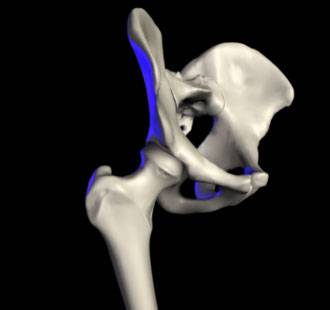

Die Orthopädie ist ein medizinisches Fachgebiet, das sich mit der Prävention, Diagnose und Behandlung von Erkrankungen und Verletzungen des Bewegungsapparates beschäftigt. Knochen, Gelenke, Muskeln, Sehnen und Bänder müssen gemeinsam funktionieren, um uns Beweglichkeit und Stabilität zu ermöglichen.

Auf unserer Seite finden Sie umfangreiche Informationen zu orthopädischen Beschwerden und Erkrankungen. Von der Arthrose über Bandscheibenvorfälle bis hin zu Kreuzbandriss und weiteren Sportverletzungen: wir geben Ihnen einen Überblick über die häufigsten orthopädischen Krankheitsbilder, wie sie behandelt werden können und inwieweit ein Bildgebungsverfahren, wie eine (z.B. MRT Knie, Rücken MRT) bei der Diagnose bei der Diagnose unterstützend wirken können.

Unsere Liste zu den häufigsten orthopädischen Problemen ist alphabetisch von A-Z geordnet. So finden Sie schnell und unkompliziert den Beitrag, der Ihnen weiterhilft. Von Krankheiten, über Verletzungen bis hin zu schmerzhaften Zuständen wie Arthrose, Meniskusschaden und Schleimbeutelentzündung – hier finden Sie die wichtigsten Informationen.